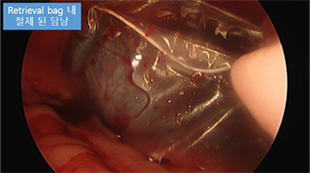

일산동물의료원은 보다 안전하고 정확한 초정밀 수술을 위해

올림푸스사의 3D 복강경 플렉시블 스코프 라인업의 최신 모델을 도입했습니다.

스코프 팁이 상하좌우로 구부러져 장기 뒤쪽까지 시야 확보가 가능하고,